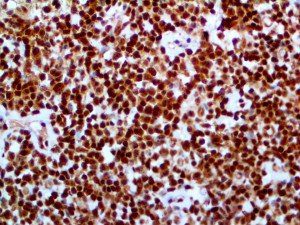

It is the ICU physician who is most likely to witness one of the deadliest manifestations of the abnormal immunological response, the cytokine storm syndrome (CSS). This response is also referred to by some as the cytokine release syndrome (CRS). CSS is characterized by continuous activation and expansion of macrophage and lymphocyte populations, which secrete large amounts of cytokines, causing the cytokine storm. This massive cytokine release is akin to hemophagocytic lymphohistiocytosis (HLH) disease, a syndrome characterized by initial unchecked and persistent activation of cytotoxic T lymphocytes and NK cells.

Clinical and laboratory manifestations of HLH include fever, enlarged liver and/or spleen, neurologic dysfunction, coagulopathy, liver dysfunction, cytopenias (i.e., low levels of erythrocytes, leukocytes, and/or platelets), hypertriglyceridemia, hyperferritinemia, hemophagocytosis, and eventually diminished NK cell activity as the immune system becomes progressively paralyzed. HLH can be familial (primary HLH) or secondary to another disease process (sHLH), such as rheumatic disease, in which it is referred to as macrophage activation syndrome (MAS, characterized by elevated ferritin).